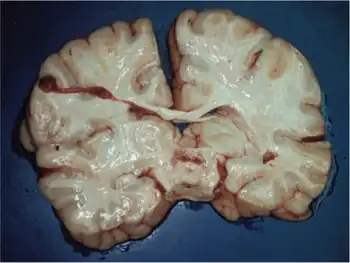

Reddish, sunken foci within the pons

The characteristic symptoms of Leigh syndrome are at least partially caused by bilateral, focal lesions in the brainstem, basal ganglia, cerebellum, and other regions of the brain. The lesions take on different forms, including areas of demyelination, spongiosis, gliosis, necrosis, and capillary proliferation.[7]